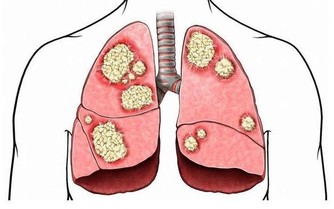

危害嚴重的眼底出血

眼底出血是指眼內視網膜出血,或玻璃體內積血。此現像只靠肉眼是看不到的,早期也可無明顯表現,需通過專業的眼底檢查才能發現異樣,相比眼表出血危險性也更大。

眼底出血原因

眼底出血不是一種獨立的眼病,而是許多眼病和某些全身性疾病所共有的特性。以下四類人群尤其要注意眼底出血狀況:

高血壓

眼底的血管比較細小,抗壓能力也小,而升高的血壓會刺激柔軟的視網膜動脈血管,造成視網膜動脈的痙攣,就容易誘發出血、視力減退甚至失明。

有研究表明眼底視網膜動脈和整個眼底的改變與血壓水平成正比,和舒張壓的關係尤其密切。

因此高血壓患者可以通過檢查眼底,明確病情的進展程度。

糖尿病

有研究表明,在糖尿病前期,約10%的患者會發生眼底病變;而眼底正常的糖尿病患者,每年約5%-10%的人會出現眼底血管增生。

視網膜的血管處於高糖環境中,相對也變得脆弱,就像老化的水管,容易發生滲漏、出血。

老年黃斑變性患者

色素上皮層下有活躍的新生血管,而新生血管較脆弱,極易破裂而引起黃斑出血。

另外,高度近視患者,視網膜變薄,周邊易發生病變,誘發新生血管,引起黃斑出血。